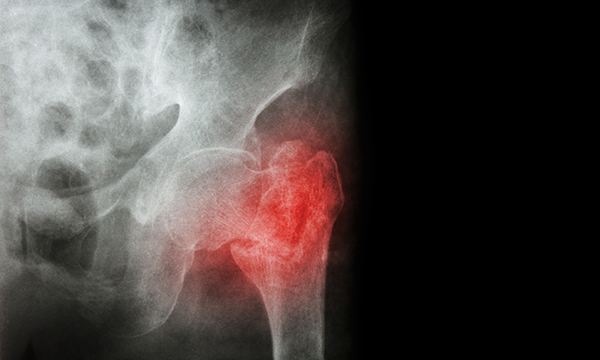

Older people who experience a hip fracture have an increased risk of dying both immediately after the fracture and in the longer term, say researchers.